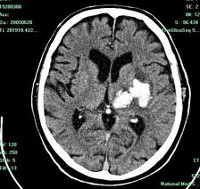

• КТ головного мозга. На томограммах внутримозговая гематома выглядит как очаг гомогенной плотности округлой или овальной формы. Если гематома возникла из-за ушиба головного мозга, она обычно имеет неровные контуры. Со временем плотность гематомы уменьшается до изоплотного состояния, соответствующего плотности мозговой ткани. Для малых гематом этот процесс занимает 2-3 недели, для средних — до 5 недель.

В диагностике нейровизуализация играет важную роль. Первоначально для исследования головного мозга назначают компьютерную томографию (КТ). Этот доступный метод позволяет быстро определить наличие крови в веществе головного мозга, а также расположение и объем сгустка. Информативность КТ максимальна через 2-3 недели после появления гематомы (максимум 5 недель). В этот период участок внутримозговой гематомы (ВМГ) имеет повышенную плотность, что облегчает диагностику, и можно ограничиться одной КТ.